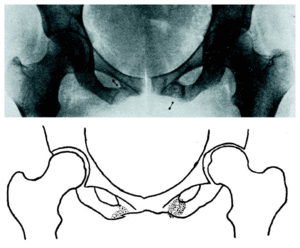

A este tipo de lesiones óseas nunca va asociada ninguna anormalidad demostrable del esqueleto óseo, ni con raquitismo, sífilis, tuberculosis u otra enfermedad orgánica. Es más frecuente en hombres que en mujeres, y las edades en que suelen aparecer oscilan entre los siete y los veintidós años. Su localización (fig. 1) es diversa y parece típica de estas lesiones; según la estadística de Asal, que recoge 590 lesionados de este tipo, 488 eran de los metatarsianos medios; 70, de la tibia; 12, del peroné; 8 de la diáfisis del fémur; 6, del cuello del fémur; 3, del calcáneo, y 3, de la pelvis. En cuanto a la localización en los metatarsianos, según las estadísticas militares alemanas, el 90 por 100 afecta al segundo y tercer metatarsiano, que son los que durante la marcha sufren la carga máxima, mientras que en el primero y quinto metatarsiano son muy raras; con alguna mayor frecuencia que éstos, se fractura el cuarto, y, aunque generalmente hay una sola fractura, a veces son dos los huesos fracturados, y, excepcionalmente, tres.

Figura 1.

La radiografía (fig. 2) nos sorprende con una imagen doble de fractura de la rama isquiopúbica. En el lado izquierdo existe un callo redondeado de mayor transparencia a los rayos X en su parte central. En el lado derecho la imagen es la de una fractura reciente, incompleta, con decalcificación de la zona ósea a cuyo nivel asienta la fractura.

Figura 2.

La ausencia de un traumatismo reciente capaz de producir estas lesiones y la disparidad evolutiva de las mismas, en ambos lados, nos conduce al diagnóstico de fractura lenta en ambas ramas isquiopúbicas.